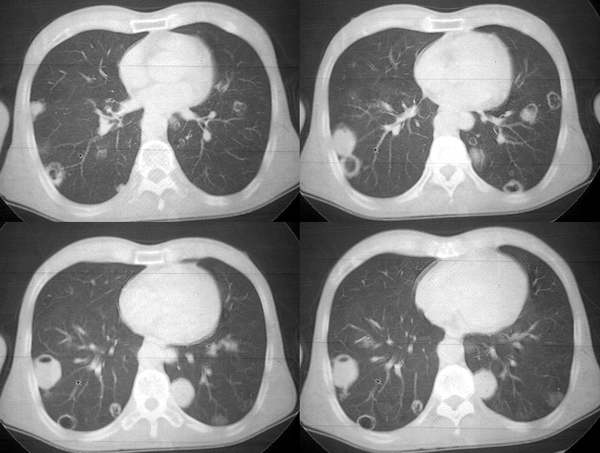

男62肺癌治疗后复查

具体治疗措施不清楚,治疗前空洞很少,请讨论空洞的性质

双肺内及胸壁旁见有多发软组织实性阴影和空洞,实性病变多见有脐凹切迹,贴近胸膜的见有胸膜凹陷征;空洞的壁多为厚薄不均,形态不规则,纵隔内见有较多肿大淋巴结,诊断为双肺内转移性病变。

双肺内及胸壁旁见有多发软组织实性阴影和空洞,实性病变多见有脐凹切迹,贴近胸膜的见有胸膜凹陷征;空洞的壁多为厚薄不均,形态不规则,纵隔内见有较多肿大淋巴结,诊断为双肺内转移性病变。[气囊或孔洞实为腺癌缘肺泡壁生长所致]

右肺门软组织块影,右主支气管及中间段支气管管壁明显增厚,两肺内多发结节及大小不等的类圆形薄壁空洞,纵隔内多发肿大的淋巴结;

考虑:1.右中央型肺癌伴两肺广泛性转移及纵隔转移。

2.多发性空洞需和霉菌性空洞鉴别。